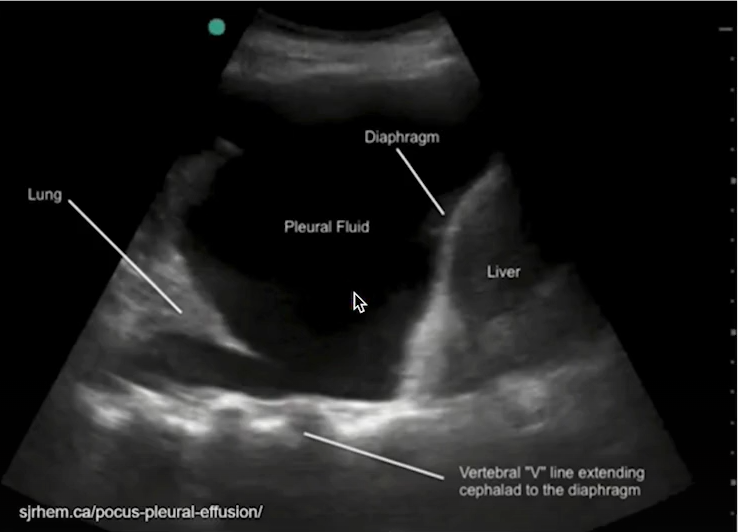

Ultrassom no derrame pleural:

A